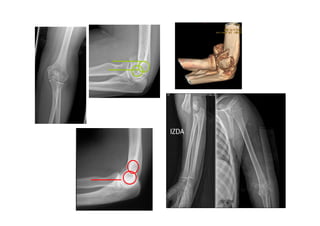

5.4 Luxaciones decodo • Clínica: – Tumefacción, dolor y pseudoparálisis brazo. – Deformidad codo – Exploración vasculonerviosa : arteria braquial • Tipos: – Luxación posterior: la más frecuente (caída con brazo extendido). Olécranon a posterior. – Luxación anterior: rara. Suele ser abierta, vigilar desgarro art. Radial. – Luxación divergente: muy rara. – Fracturas – luxaciones. • Trto: – Reducción cerrada – Inmovilización tres semanas y citar en cext. traumatología 3 sem.

5.2 Fracturas decabeza de Radio: • 20-30% de las fracturas del codo. • Mecanismo lesional: Generalmente traumatismos indirectos al caer sobre la mano en extensión. • Clínica: dolor selectivo a la palpación de la cabeza de radio, que se acentúa con la prono-supinación

• Clasificación deMason modificada: – I: • Parcelar <30 % , sin desplazamiento o < 2mm. • Pronosupinación limitada por el dolor y la tumefacción. • No hay bloqueo articular. – II: • Parcelar > 30% con desplazamiento > 2mm. • Puede haber bloqueo mecánico de la articulación. • Angulación >30º. – III: conminuta. – IV: Fracturas asociadas a luxación del codo.

5.3 Fracturas deolécranon: – Mecanismo lesional: Impacto directo sobre el olécranon con el codo en flexión. – Dolor, tumefacción, edema sobre el olécranon, clínica por afectación del nervio cubital. Palpación de un surco en el lugar de la fractura. – Impotencia para extensión de codo contra gravedad Clasificación de Colton: -No desplazadas o estables: Inmovilización del codo con férula de escayola 3-4 semanas con movilización precoz, evitando la flexión >90º hasta la 6ª semana. En los ancianos mover a la 3ª sem. No usar inmov en ext.pq > rigidez y significa necesidad de IQ. -Desplazadas: Por avulsión. Oblicuas y trasnversales. Conminutas. Fract/ luxación

Pronación dolorosa • Másfrec. en niñas de 2-3 años (raro en >5ª) • Mecanismo lesional: pronación y tracción forzadas con el brazo extendido. • Clínica: brazo extendido y pronado, con el antecedente de tracción. • Rx: normal. Trto: Invertir los movimientos que lo han causado: Supinación + flexión + presión sobre la cabeza del radio